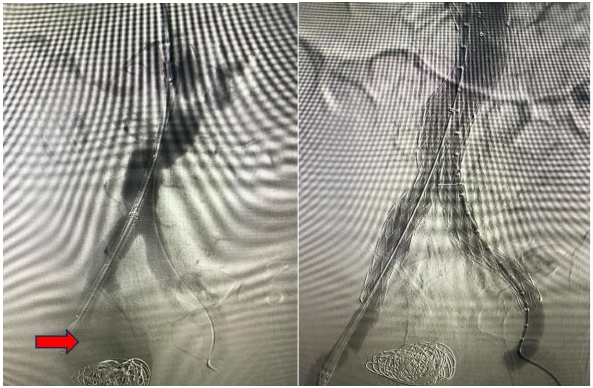

术中左图造影提示右侧髂内动脉瘤,右图复查造影动脉瘤未显影

术中行“腹主动脉、双侧髂动脉造影+覆膜支架腔内隔绝+右侧髂内动脉栓塞”,术后再次造影提示腹主动脉和双侧髂外动脉通畅,右侧髂内动脉瘤不显影,右侧髂内动脉栓塞良好。